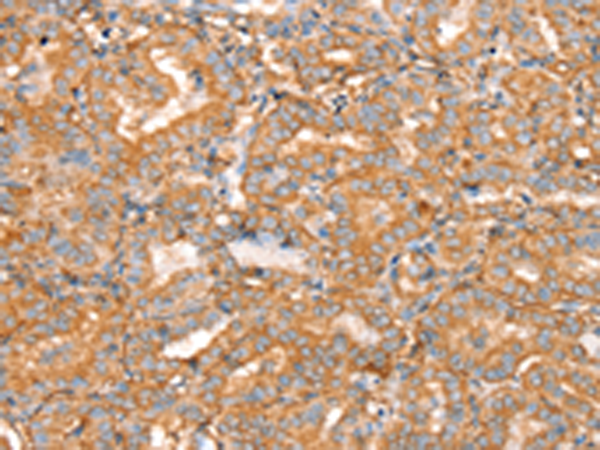

分类: 科研抗体货号: P12181别名: NCKX3应用: IHC反应种属: Human, Mouse, Rat